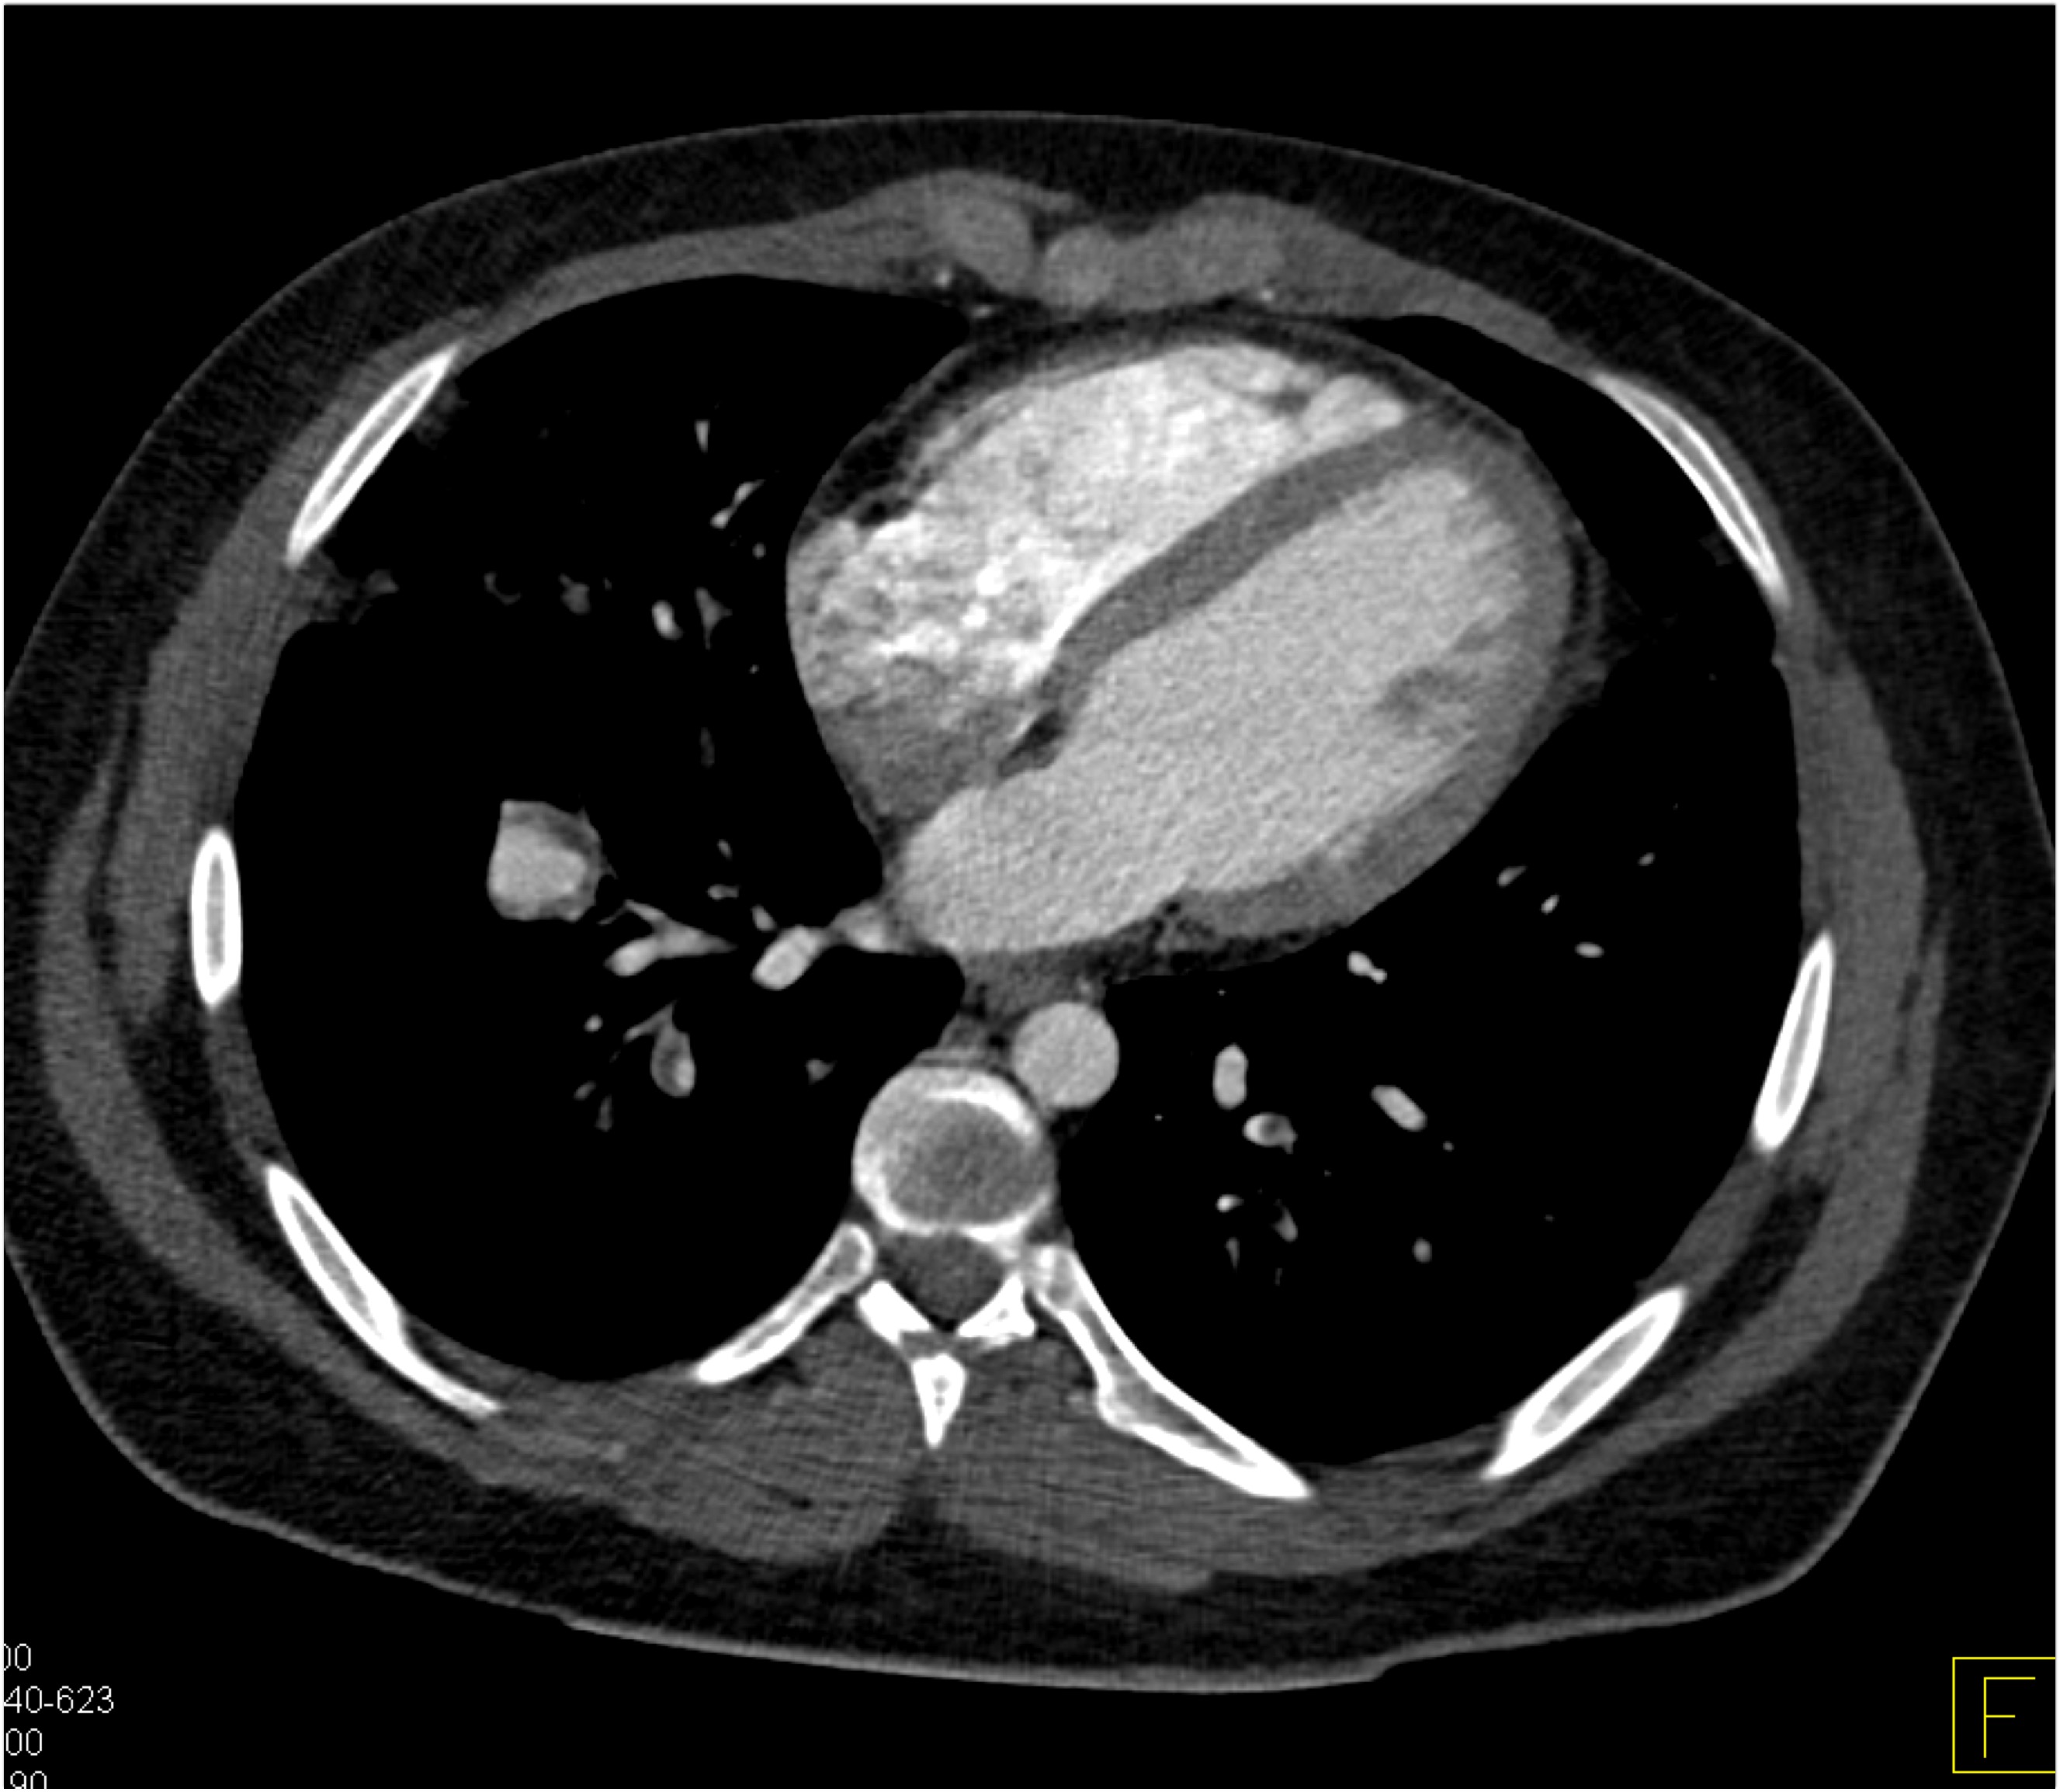

7) In this patient with mediastinal widening on CXR the best diagnosis is?

lymphoma

mediastinal lipoma

bronchogenic cyst

duplication cyst